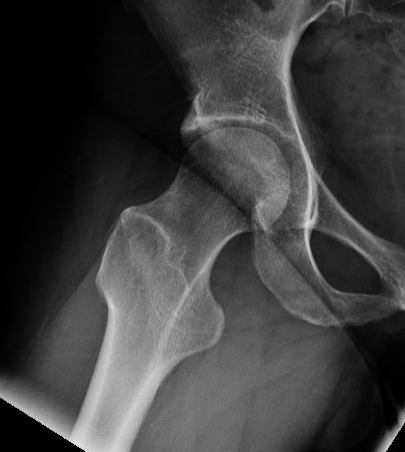

45 and 90 degree Dunn view

Look for Cam morphology

Small Cam on Dunn view Large anterior Cam on Dunn view